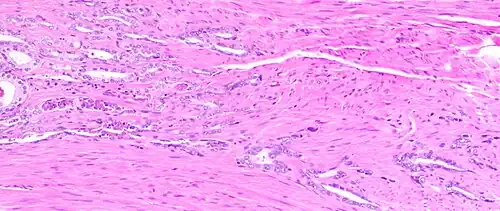

The connective tissue of the prostate is made up of fibrous tissue and smooth muscle.[2] The fibrous tissue separates the gland into lobules.[2] It also sits between the glands and is composed of randomly orientated smooth-muscle bundles that are continuous with the bladder.[11]

Histology of prostate with gradually increasing simple atrophy from left to right, H&E stain. Crowding and angulation may mimic that of adenocarcinoma, but there is nuclear basophilia rather than atypia, and occasional basal cells can still be seen.